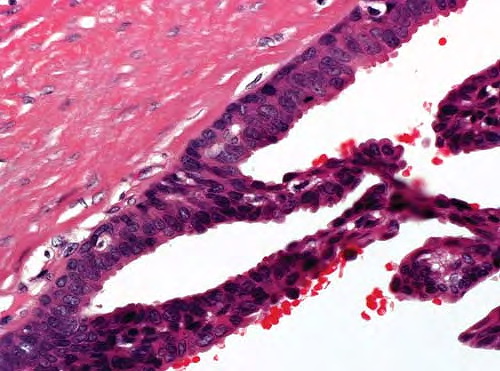

Digital papillary adenocarcinoma = غدوم حطاطي على الاصبع